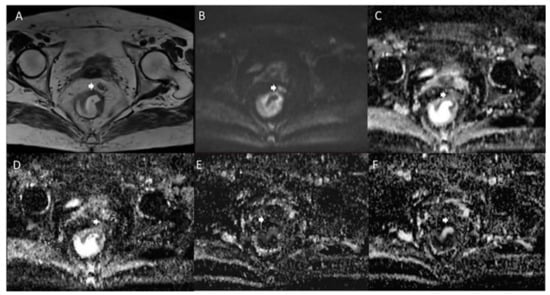

- Yu, X.; Wen, L.; Hou, J.; Bi, F.; Hu, P.; Wang, H.; Wang, W. Discrimination between Metastatic and Nonmetastatic Mesorectal Lymph Nodes in Rectal Cancer Using Intravoxel Incoherent Motion Diffusion-Weighted Magnetic Resonance Imaging. Acad. Radiol. 2016, 23, 479–485. [Google Scholar] [CrossRef] [PubMed]

- Qiu, L.; Liu, X.; Liu, S.; Weng, Z.; Chen, X.; Feng, Y.; Cai, X.; Guo, C. Role of Quantitative Intravoxel Incoherent Motion Parameters in the Preoperative Diagnosis of Nodal Metastasis in Patients with Rectal Carcinoma. J. Magn. Reson. Imaging 2016, 44, 1031–1039. [Google Scholar] [CrossRef]

- Long, L.; Zhang, H.; He, X.; Zhou, J.; Guo, D.; Liu, X. Value of Intravoxel Incoherent Motion Magnetic Resonance Imaging for Differentiating Metastatic from Nonmetastatic Mesorectal Lymph Nodes with Different Short-Axis Diameters in Rectal Cancer. J. Cancer Res. Ther. 2019, 15, 1508. [Google Scholar] [CrossRef]